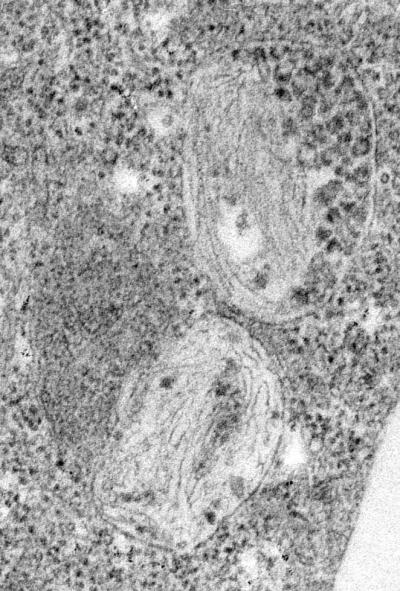

image: Fibrils forming within endosomes of non-pigment cells containing Pmel17 view more

Credit: (Credit: Berson et al. J. Cell Biol., 161:521-33, 2003)

Before the fibers are laid down, the researchers found in the Developmental Cell study that Pmel17 passes through a series of compartments called endosomes, much the way proteins that are tagged for degradation do. They determined that this process also happens in non-pigment cells. This discovery indicates that sorting is not a melanocyte-specific process; the sorting phenomenon is a general one.